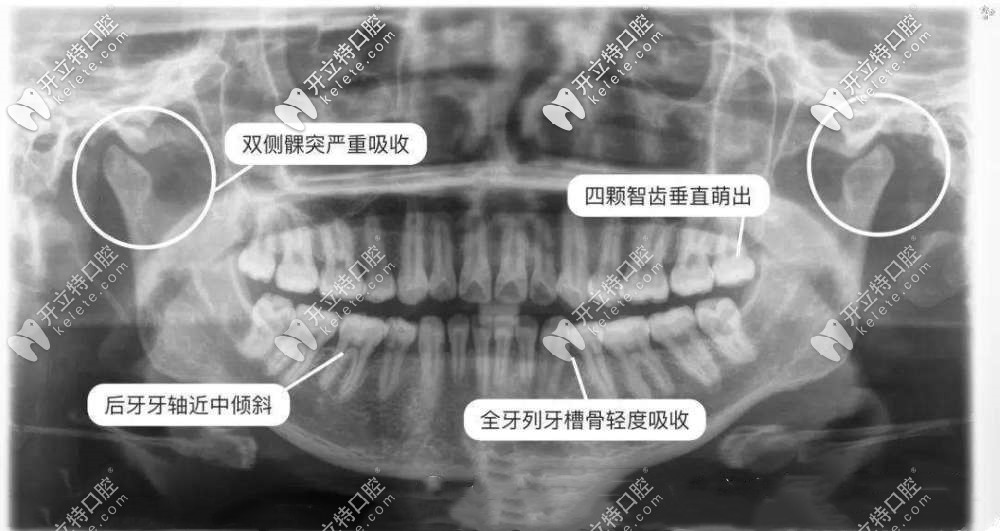

拍牙齒x光片能看出智齒的情況、齲壞的情況等,而一般拍一次x光片的價格根據(jù)類型不同,其價格也在在幾十到幾百不等,下面小編會給大家詳細(xì)介紹下,感興趣的小伙伴們快來看看吧。

口腔中的牙片由以下幾種組成:小牙片、全景片,頭顱側(cè)位片、牙科CT,不同牙片的區(qū)別主要是看的牙病不同,比如小牙片看單個牙齒情況,頭顱側(cè)位片用于正畸,全景片和牙科CT做種植牙用。